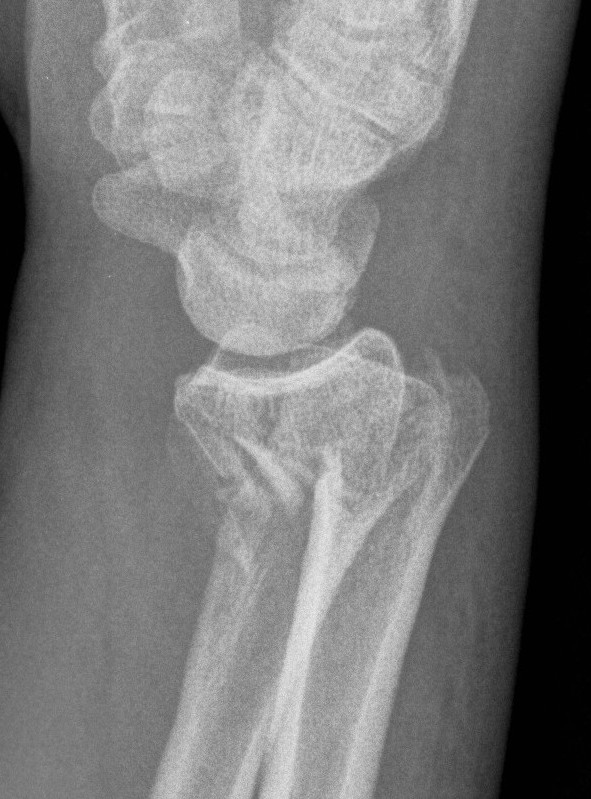

Radial angles

| Volar tilt mean 11° | Radial inclination mean 22° | Radius mean 11 mm longer than ulna |